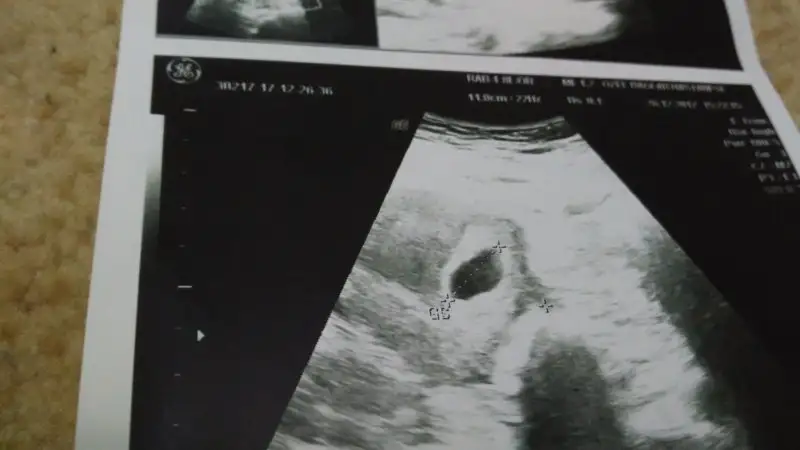

Canim kacinci haftdasinEki Görüntüle 2085142 Eki Görüntüle 2085143 Eki Görüntüle 2085144 Eki Görüntüle 2085145 Eki Görüntüle 2085146 Eki Görüntüle 2085143 Eki Görüntüle 2085142 Eki Görüntüle 2085143 Eki Görüntüle 2085144 Eki Görüntüle 2085145 Eki Görüntüle 2085146 Eki Görüntüle 2085147 Eki Görüntüle 2085147 Eki Görüntüle 2085146 Eki Görüntüle 2085142 Eki Görüntüle 2085143 Eki Görüntüle 2085144 Eki Görüntüle 2085145 Eki Görüntüle 2085146 Eki Görüntüle 2085147 Eki Görüntüle 2085146 Eki Görüntüle 2085147 Eki Görüntüle 2085145